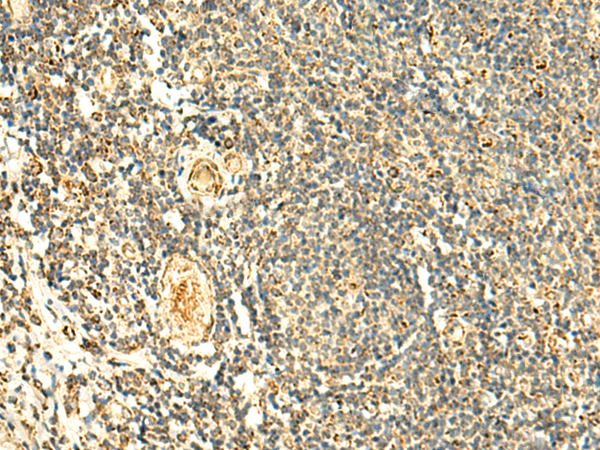

IHC positive control: |

Human colorectal cancer and Human tonsil |

IHC Recommend dilution: |

50-300 |